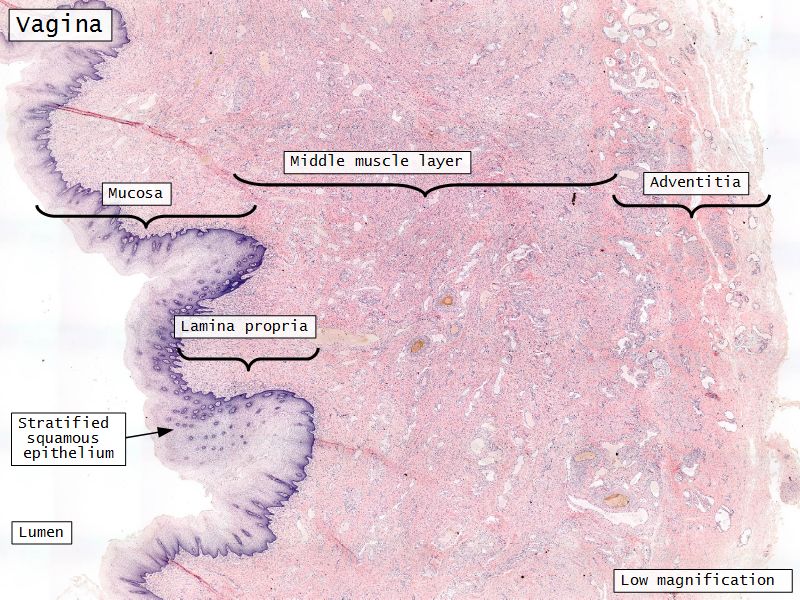

Vagina

Slide 90

Vagina

- Fibromuscular tube with 3 layers

- Inner mucosa

- Middle muscle layer

- External adventitia

Mucosa

- Epithelium

- Thick stratified squamous nonkeratinized

- Lamina propria

- Fibroelastic connective tissue

- Rich in elastic fibres

- Contains lymphoid elements

- Deep portion highly vascular

- No glands

Muscle layer

- Thin inner circular

- Thick outer longitudinal

- External orifice ring of skeletal muscle

Adventitia

- Fibroelastic connective tissue

- Fixes onto surrounding structure

- Blood vessels and nerves